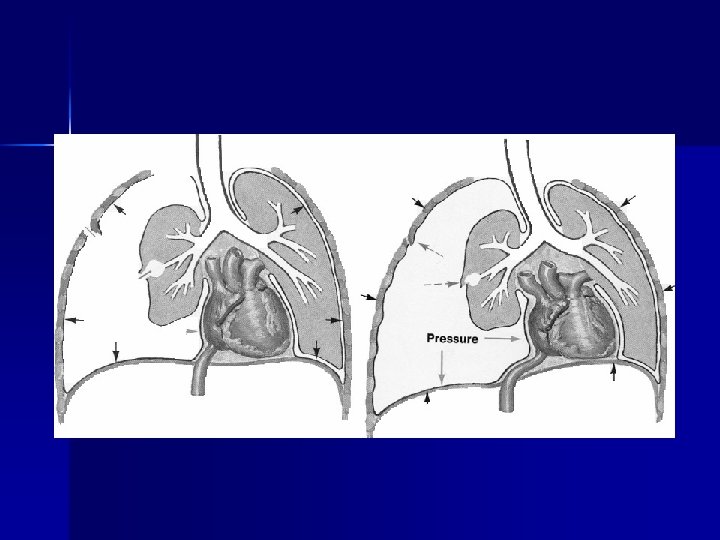

n n n n Cianosis Esfuerzo ventilatorio intenso Ingurgitación yugular de ruidos respiratorios Neumotórax a tensión Diagnóstico: Clínico-inmediato NO x Rx Aguja: 2 do espacio intercostal línea clavicular media Sello Tórax: 5 to espacio intercostal línea axilar media Tórax inestable: TET Presión positiva Peso sobre lesión